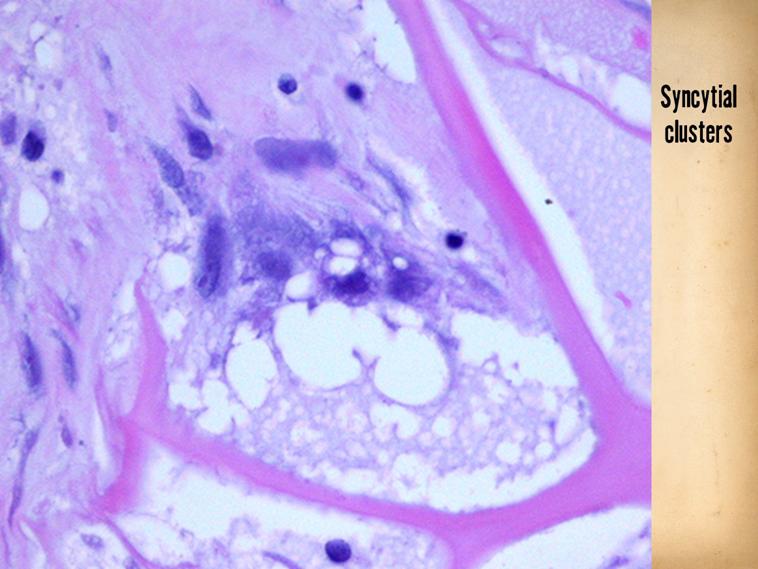

LEFT - The reasons why the material induces embryonic activities can be studied in other resources (at Arimedica.com).  This slide shows a key piece of evidence - the syncytial fibroblast, which is the embryonic dermatoblast, a cell which NEVER - not ever - appears in a normally healing wound.

SLIDE SUMMARY:  The basis for Integra CGM’s biological effects is understood in many ways.  This illustrates a key component: the matrix is developing a cluster of syncytial fibroblasts.  This is the embryonic dermatoblast, a cell which NEVER appears in normal wound post-inflammatory repair.

------------------------------------------------------------------------------------------------------------------------------------

Here is a close up of another syncytial cluster.  The small pioneer cells, seen on the previous slide, proliferate into small clusters like this, composed of several syncytial fibroblasts. which are starting to make young fibrillar collagen (pale pink), nestled within a pore or domain of the matrix.  Some other not-yet-transformed lymphoid progenitor cells are also present (they must bind to the matrix to begin the process, an effect of the aminoglycan in the material).